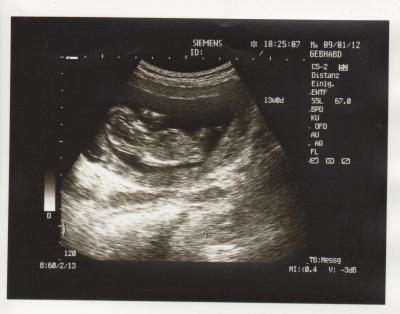

Da ja jetzt die Bilder wieder gehen, schnell mein US-Bild :-) !!!

Hatte ja letzte Woche FA Termin, Kind ist zeitgerecht entwickelt, Nackenfalte super 0,8 und ist ca. 6,7 cm groß. Leider konnte man das Geschlecht noch nicht erkennen, war wohl noch zu früh Hoffe am 30.01. sieht man was, da bin ich dann in der 16. Woche